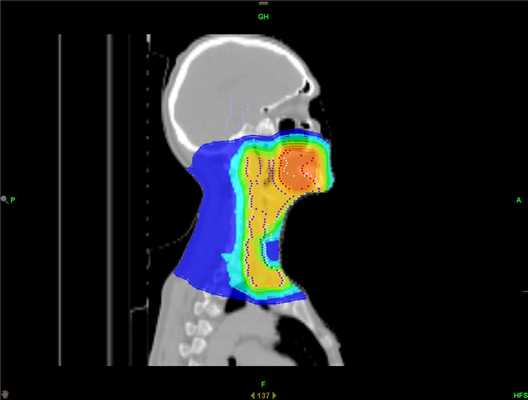

- Фотонная терапия. Именно этим видом излучения проводится лучевое лечение большинства онкологических пациентов в современном мире. Достаточно высокая проникающая способность в сочетании с высокотехнологичными способами подведения дозы (IMRT и VMAT), достаточно совершенные системы планирования позволяют очень эффективно использовать этот вид излучения для лечения пациентов с приемлемыми показателями токсичности.

Затем врач-радиотерапевт рисует объёмы облучения и критических структур (тех, на которые будет предписано ограничение дозы) на полученных срезах КТ с учётом данных других диагностических модальностей (МРТ, ПЭТ). Далее формируется задача для медицинского физика, включающая определение доз, которые должны быть подведены к мишени, мишеням или отдельным её частям, а также тех, которые не должны быть превышены в объёмах здоровых органов и тканей. Медицинский физик разрабатывает дозиметрический план в соответствии с заданными параметрами, при соблюдении которых и успешной верификации данного плана на фантоме, можно считать пациента готовым к лучевой терапии.

Использование дистанционной лучевой терапии сопровождается двумя проблемами: повреждение здоровых тканей и недостаточная регрессия новообразования. Побочные эффекты при этом иногда полностью нивелируют достигнутый результат лечения и увеличивают риск развития послеоперационных осложнений. Решить эти проблемы и увеличить эффективность радиологического лечения способна лучевая терапия с модулированной интенсивностью (IMRT), и в частности технология TomoTherapy HD.

TomoTherapy HD — комплекс, объединяющий компьютерный томограф и современный ускоритель частиц. Система позволяет точно доставить дозу радиации в опухоль какой бы сложной формы она ни была (локализовать опухоль, запланировать лечение и проводить его), оберегая от лучевой нагрузки здоровые ткани. Такой подход позволяет значительно снизить риск нежелательных проявлений.

Возможность подать дозу радиации с минимальным воздействием на здоровые ткани позволяет оказать более выраженное влияние на опухоль и снизить вероятность выраженных побочных эффектов в будущем